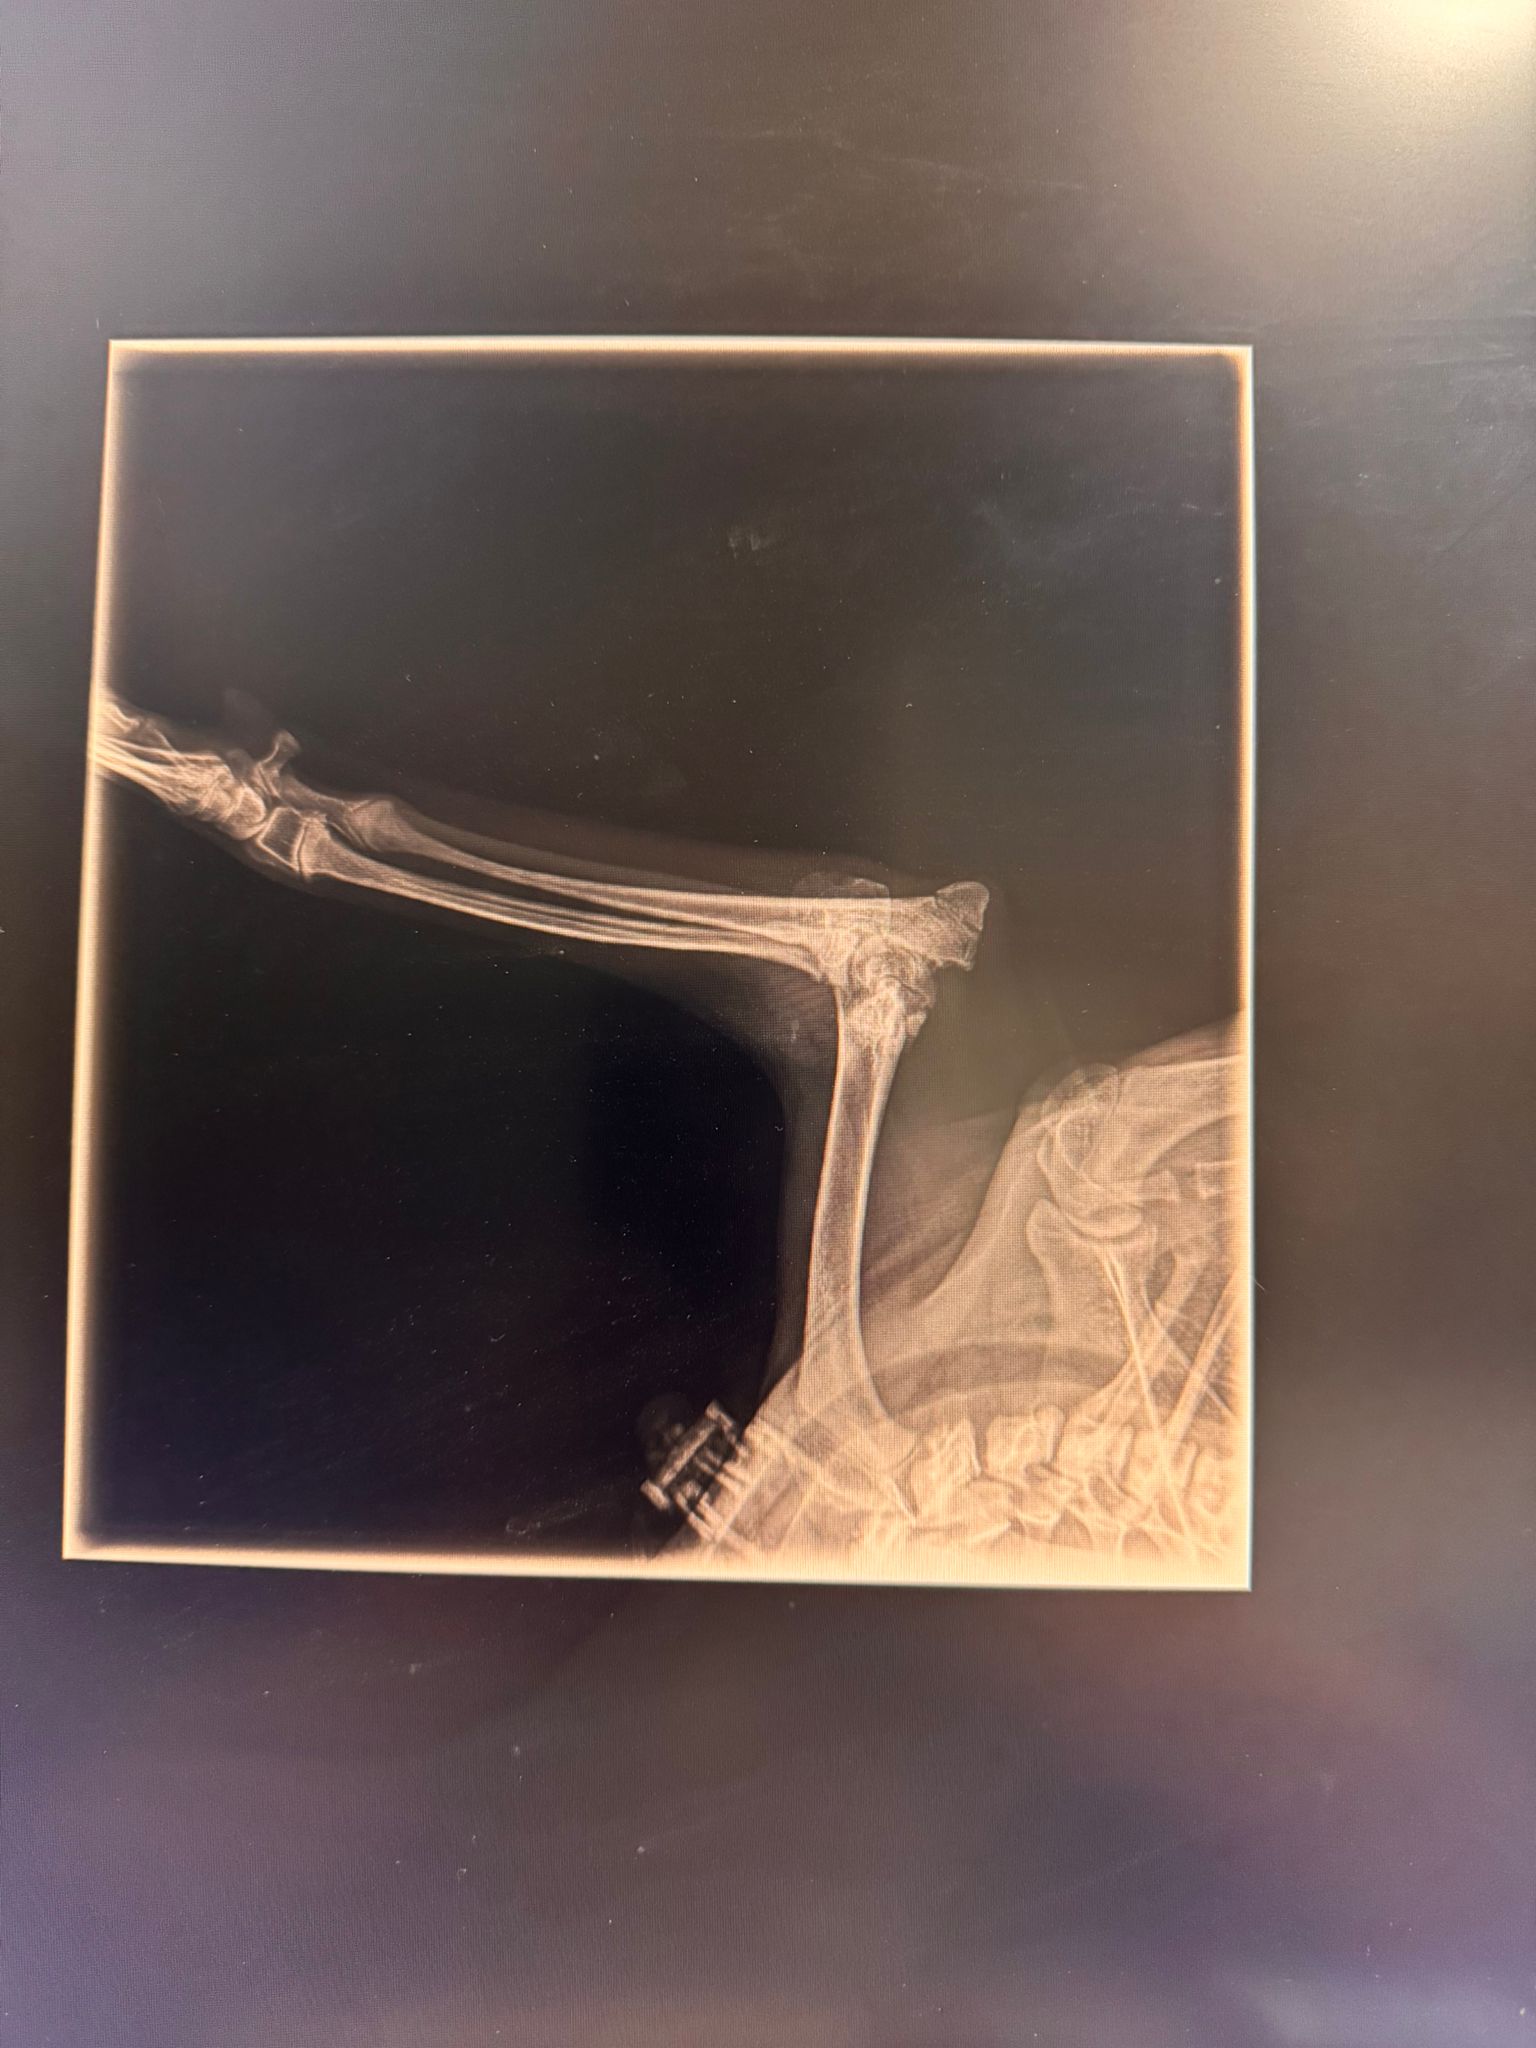

Fractura bilateral de cóndilo lateral, Salter-Harris tipo 4

Y es que Cancho ha sufrido un fuerte traumatismo siendo muy bebé; esto suele pasar cuando caes de una altura considerable. Sus dueños decidieron abandonarlo, la perrera lo recogió y de ahí nos llamaron. Os prometemos que hemos corrido todo lo posible, pero esta vez hemos llegado tarde; no sabemos cuándo fue este golpazo, pero lo que sí sabemos es que ha pasado demasiado tiempo como para poder reparar sus fracturas.

Hoy, durante la cirugía, los pequeños huesos estaban destrozados y llenitos de artrosis. Y no, esta vez tenemos que contaros que no hay reparación posible y que nuestro chico guapo deberá aprender a caminar así.